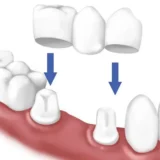

Hiện nay, cấy ghép implant đang là giải pháp nha khoa tốt nhất cho người mất răng. Với sự phát triển theo thời gian, nhiều hãng sản

Hiện nay, trồng răng Implant là một phương pháp phục hình răng được khuyến khích thực hiện. Phương pháp này được thực hiện để duy trì khả